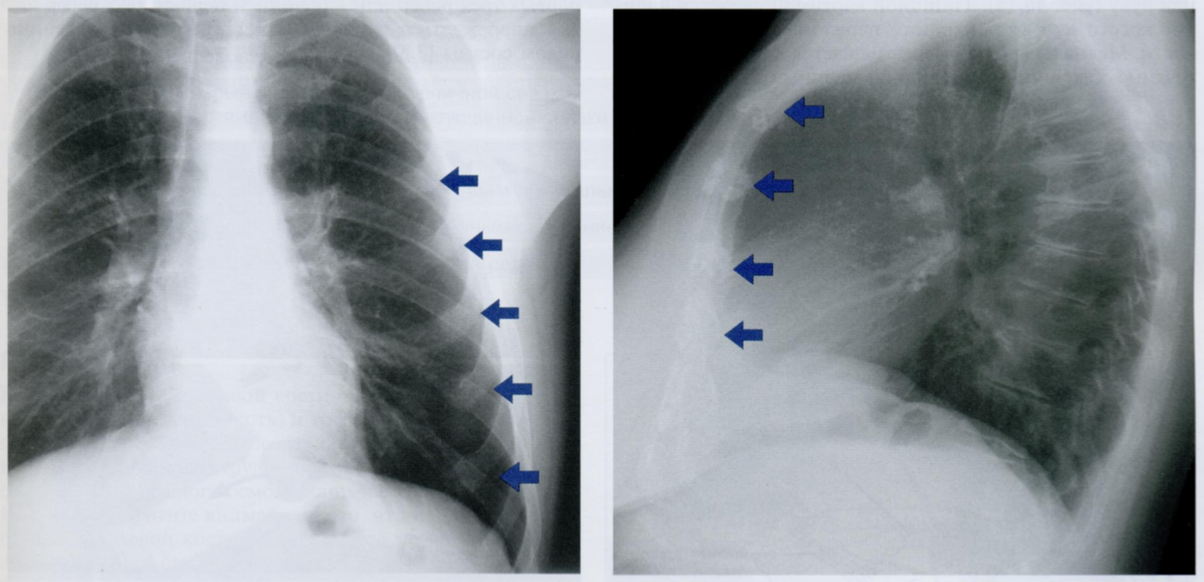

Оцените ассиметричность мягких тканей на снимке.

Обратите внимание на тень молочной железы (стрелочки), оцените симметричность теней слева и справа.

Ассиметрия прозрачности может наблюдаться после мастэктомий, радикального иссечения шейных лимфатических узлов, посттравматической гематомы грудной стенки, гепертрофии/атрофии мышц.

Пациентка после левосторонней мастэктомии с просветлением в нижних отделах с соотвествующей стороны (звездочка) в связи с отсутствием молочной железы (стрелочки).

Если есть сомнения, можно внимательнее рассмотреть подмышечную область на предмет возможного наличия металических клипс после иссечения ЛУ подмышечной впадины (фото ниже).

Ключевой момент - не ошибиться, принимая уменьшение прозрачности с одной стороны за выпот или внутрилегочное образование.